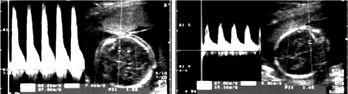

Εγκεφαλικές αρτηρίες

Με το Doppler εξετάζονται οι κύριες εγκεφαλικές αρτηρίες, όπως η έσω καρωτίδα,

η μέση εγκεφαλική, η πρόσθια και η οπίσθια εγκεφαλική (εικονα 6). Η πιο συχνά

εξεταζόμενη αρτηρία είναι η μέση εγκεφαλική, όπου το PI είναι σημαντικά μεγαλύτερο

από εκείνο των άλλων εγκεφαλικών αρτηριών (εικόνα 7). Με την πρόοδο της ηλικίας

της κύησης αυξάνεται η ταχύτητα ροής του αίματος, όπου συνεπάγεται ελάττωση

του PI.

![]() |

|

| Εικόνα 6. Εγκεφαλικές αρτηρίες. | Εικόνα 7. Μέση εγκεφαλική αρτηρία |